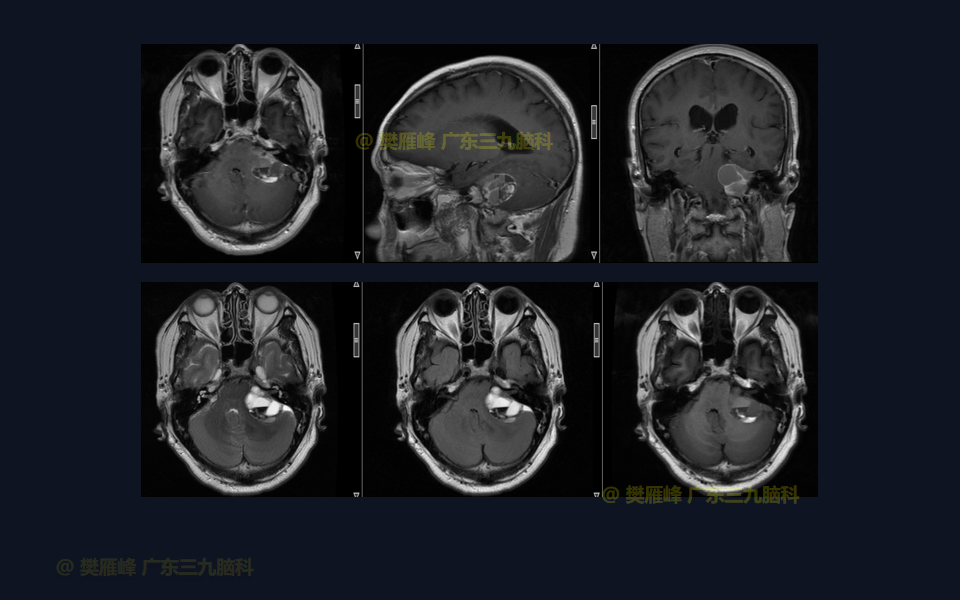

手术系列022:乙状窦后入路切除4级囊实性听神经瘤